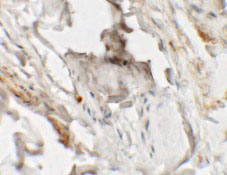

Immunohistochemistry of HHATL in human skin tissue with HHATL antibody at 2.5 μg/mL.